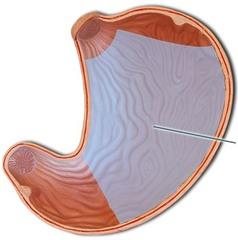

Body (of stomach)

Cardia (of stomach)

Fundus (of stomach)

Gastroesophageal sphincter

Pyloric Sphincter

Pylorus (of stomach)

Rugae (of stomach)